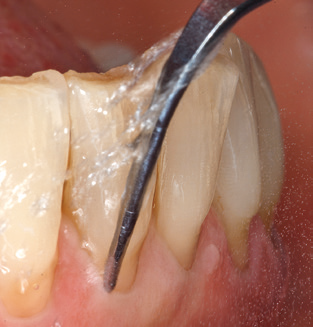

Following machine cleaning of the tooth and implant surfaces, the surfaces of the natural teeth are cleaned manually using standard hand instruments. When performing manual cleaning, particular attention must be given to maintaining the correct angle of application, appropriate sharpness, good support and working with the curette from apical to coronal. Either titanium or carbon curettes should be used for post-cleaning of the implant structures (Fig. 8). In addition to the use of ultrasonic devices, power jet devices can also be used in conservative dentistry. However, it must be taken into consideration that these procedures are not suitable for removing hard deposits and thus they cannot replace the use of hand instruments and ultrasonic instruments completely. In all cases, cleaning is followed by mechanical polishing of the accessible tooth and implant surfaces with polishing cups and polishing compounds (Fig. 9).

Fig. 4: Flexible probes with millimetre markings are recommended for the probing of dental implants (e.g. Colorvue Kit PCV11KIT6, Hu­Friedy). – Fig. 5a and b: A straight working tip (1P, W&H Dentalwerk Bürmoos GmbH) is a suitable instrument for use on all natural teeth. – Fig. 6: Curved working tips (3Pr/3Pl, W&H Dentalwerk Bürmoos GmbH) lend themselves to the processing of difficult-to-reach areas of the tooth and root surfaces (e.g. furcations). – Fig. 7: The tapered, hexagonal implant cleaning tip (1I, W&H Dentalwerk Bürmoos GmbH) permits atraumatic and efficient cleaning of the crown and abutment surfaces. – Fig. 8: Titanium and carbon curettes are suitable instruments for the manual cleaning of the implant surfaces.